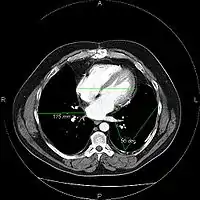

A picture archiving and communication system (PACS) is a medical imaging technology which provides economical storage and convenient access to images from multiple modalities (source machine types).[1] Electronic images and reports are transmitted digitally via PACS; this eliminates the need to manually file, retrieve, or transport film jackets, the folders used to store and protect X-ray film. The universal format for PACS image storage and transfer is DICOM (Digital Imaging and Communications in Medicine). Non-image data, such as scanned documents, may be incorporated using consumer industry standard formats like PDF (Portable Document Format), once encapsulated in DICOM. A PACS consists of four major components: The imaging modalities such as X-ray plain film (PF), computed tomography (CT) and magnetic resonance imaging (MRI), a secured network for the transmission of patient information, workstations for interpreting and reviewing images, and archives for the storage and retrieval of images and reports. Combined with available and emerging web technology, PACS has the ability to deliver timely and efficient access to images, interpretations, and related data. PACS reduces the physical and time barriers associated with traditional film-based image retrieval, distribution, and display.

Most PACS handle images from various medical imaging instruments, including ultrasound (US), magnetic resonance (MR), Nuclear Medicine imaging, positron emission tomography (PET), computed tomography (CT), endoscopy (ES), mammograms (MG), digital radiography (DR), phosphor plate radiography, Visible Light Photography (VL), Histopathology, ophthalmology, etc. Additional types of image formats are always being added. Clinical areas beyond radiology; cardiology, oncology, gastroenterology, and even the laboratory are creating medical images that can be incorporated into PACS. (see DICOM Application areas).